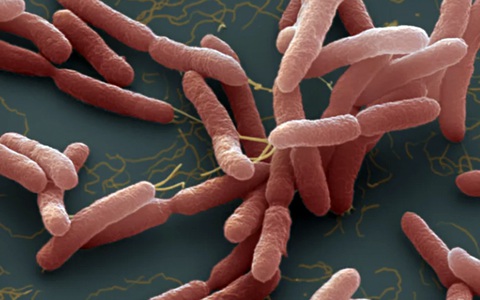

Rất nhiều ca nhiễm và tử vong do "vi khuẩn ăn thịt người" (bệnh Whitmore). Bệnh khó chẩn đoán và nhiều người còn chưa biết đến căn bệnh chết người này để phòng tránh.

CDC đã đưa ra khuyến cáo đối với các cơ sở y tế sau khi lần đầu tiên phát hiện vi khuẩn Burkholderia pseudomallei gây bệnh Whitmore trong mẫu đất và nước ở Mỹ.

TTO - Trường hợp bé gái 9 tuổi ở Đắk Lắk bị nhiễm Whitmore (do vi khuẩn Burkholderia pseudomallei gây ra, còn gọi 'vi khuẩn ăn thịt người') lại dấy lên nỗi lo lắng khi chúng xâm nhập vào cơ thể, gây tổn thương nhiều cơ quan.